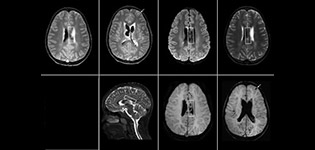

Pseudo-continuous arterial spin labeling (pCASL) was developed for brain perfusion imaging without contrast agent. “This is very desirable in pediatric patients where the general trend is to limit the administration of contrast,” says Dr. Miller. Growing confidence in specific applications “We built up confidence in pCASL by comparing it to contrast-based perfusion imaging. Once we had confidence that it was representing what the contrast perfusions were representing, we increased our diagnostic confidence by serial imaging in either the acute stage or the long term stages in a number of patients with arterial abnormalities.

Dr. Miller uses pCASL for all patients who present with chronic and acute cerebrovascular abnormalities such as acute stroke, as well as patients who present with signs of acute inflammation in the brain, and occasionally in patients with tumors, to assess the perfusion status of their tumor.

“In combination with diffusion weighted imaging, it can help give a more extended assessment of the degree of perfusion abnormality in a patient who is suffering acute ischemia. We have a number of patients who have chronic arterial insufficiency due to prior arterial abnormalities or acquired arterial abnormalities such as sickle cell disease or neurofibromatosis. Sometimes the child’s first manifestation of disease progression is a reduction in brain perfusion before stroke symptoms manifest clinically or in diffusion weighted imaging. We use pCASL to help delineate the perfusion abnormality.”

To other new users I would recommend to also start to interpret the pCASL images in comparison with other standard imaging – T2 and FLAIR and DWI – until the user gains confidence in interpreting these images by themselves.” “A powerful use of pCASL is in patients with chronic cerebrovascular stenosis, where clinicians desire information on how compensatory mechanisms of the brain are performing to enable perfusion to the brain. Often clinicians take into account how the compensatory mechanisms appear to help to provide adequate perfusion to the patient’s brain, and they may intervene surgically or make some other management decision.” “Another special application is the assessment of cerebrovascular reactivity with a Diamox perfusion exam, where we subtract two sets of pCASL images.”

“pCASL has now become more of a first-line scan for assessing perfusion for us, as opposed to DSC-based perfusion imaging with contrast agent. And in patients who were not planned to have contrast, we can perform pCASL for perfusion imaging without need to stop the exam, pull the patient out, and put in an IV. It also negates the postprocessing that’s necessary for dynamic susceptibility contrasts. And it allows us to repeat perfusion imaging in the same patient at the same imaging time, which is helpful in terms of patient motion, or in a situation where a scan needs to be done before pharmacological perfusion imaging.”